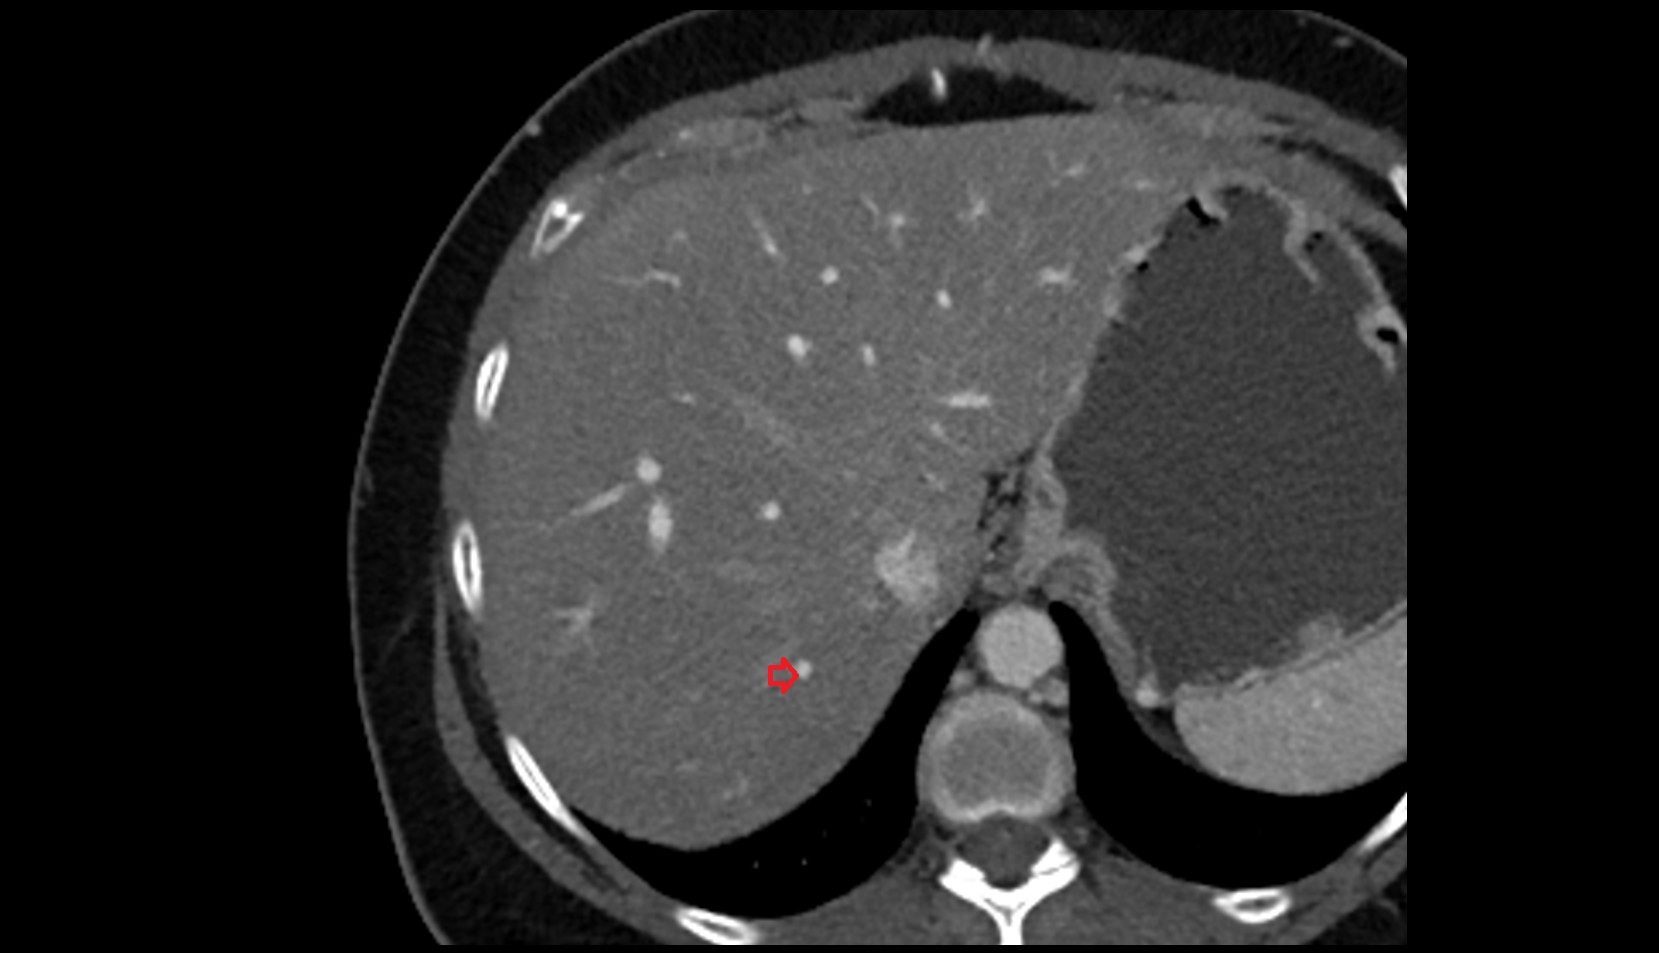

- Right lobe of liver

- Liver